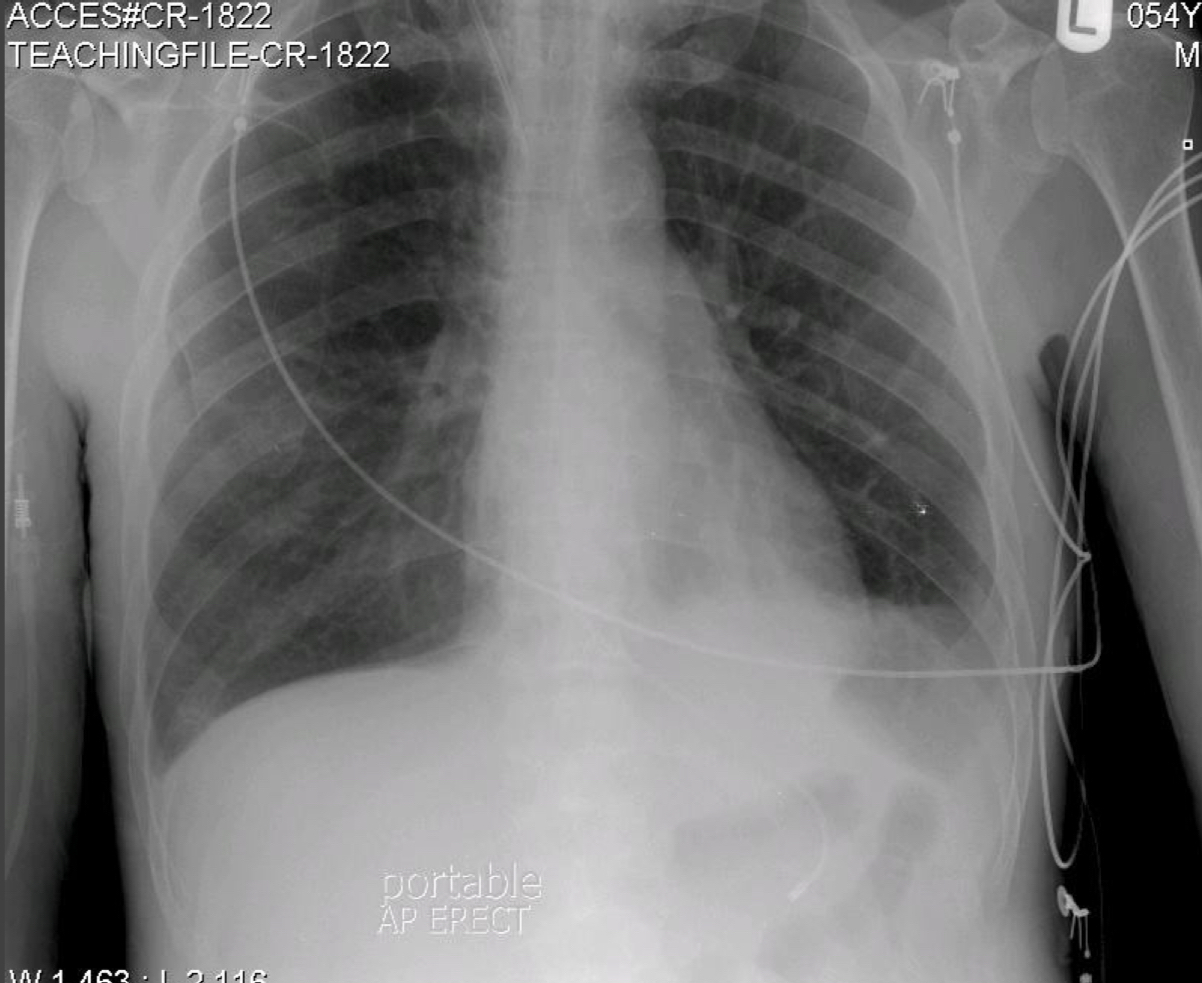

ARDS (Acute Respiratory Distress Syndrome)

“Ground glass” effect.

Multifocal bilateral airspace opacities.

Perihilar & lower zone distribution.

Central Venous Catheter

Ideal tip location: cavo-atrial junction.